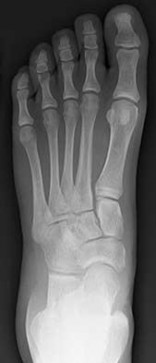

Figures 1a through 1c

Tarsal coalitions occur when primitive mesenchymal cells fail to differentiate and form the

normal articular separations between the tarsal bones of the hindfoot. Overall incidence is difficult to determine because many affected people are minimally symptomatic or asymptomatic. Symptomatic tarsal coalitions typically present in adolescents as a painful flatfoot; however, there are a number of possible presentations, and occasionally symptoms do not appear until adulthood. Most tarsal coalitions are between the calcaneus and the navicular (CN) and the talus and the calcaneus (TC). Although most TC coalitions are across the middle facet, posterior facet coalitions do occur. Plain radiographic evaluation of suspected tarsal coalition is the mainstay for diagnosis. However, coalitions can be bony or fibrous, and making the diagnosis can be difficult. The addition of CT images to distinguish bony definition and MR images to decipher soft tissue can aid in diagnostics. Bony coalitions appear as definite bony bridging between the bones, while fibrous coalitions are suspected when distortion of the bony anatomy is seen. Bony coalitions are best seen on the oblique view (CN) and Harris axial view (TC). There are a number of secondary signs such as the anteater (AE) sign (elongation of the anterior process of the calcaneus as it extends to the navicular as seen on the lateral view [CN]). talar beaking (traction spur of the talar neck thought to result from abnormal stresses as seen on the lateral view [both CN and TN]), and the “C” sign (a continuous cortical contour from the medial talus to the sustentaculum tali [ST]) as seen on the lateral view (TC). A number of newer signs are not as well known, such as a broad mediolateral dimension of the navicular on the anteroposterior (AP) view (the

navicular is wider than the talar head [CN]), nonvisualization of the middle facet on the lateral view (TC), the brick sign (a normal ST is flat, but a distorted ST is enlarged and curved [CN]), and a tapered lateral navicular bone as seen on the AP view (the medial navicular [CN] is much thicker than the lateral navicular).

Figure 1a shows talar beaking (TB), an AE, and an open middle facet (MF). Figure 1b shows a wide navicular (WN), and Figure 1c shows an abnormal articulation between the calcaneus and the navicular, all consistent with a CN coalition.